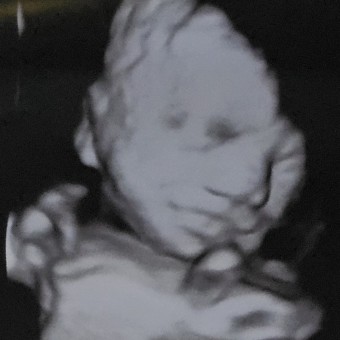

Baby Orion Matthew Allen-Taylor

Laura Allen -Taylor & Matthew Allen-Taylor

East Orange, NJ

April 1, 2026

The moment we've been waiting for BABY # 2 💜💙💜💙